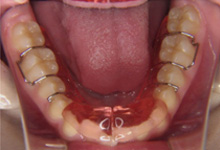

固定式矯正装置